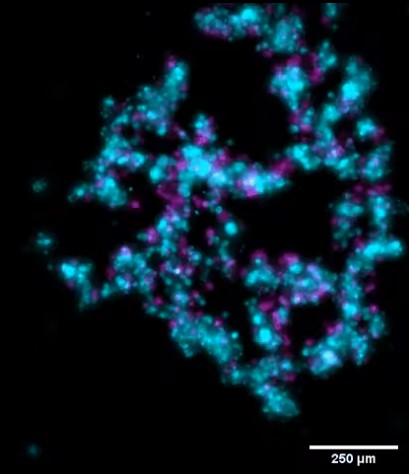

Live cell imaging of co-culture skin cancer spheroids. The patient-derived skin cancer cell line, UW-CSCC2 (magenta), and dermal fibroblasts (cyan) were seeded in ultra-low attachment plates to facilitate spheroid formation. Z-stacks of live spheroids were taken every 2h45min for 60h. This revealed the formation of a cancer shell around a fibroblastic core. Investigation of other combinations of fibroblasts and cancer cell lines indicate the formation of distinctive spatial architectures for each combination (not shown).